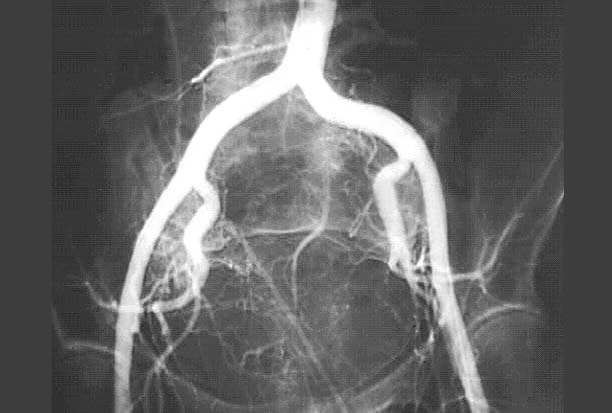

Pelvic Arteriogram

1. Aorta

2. Common iliac artery

3. Internal iliac artery

4. External iliac artery

5. Superior gluteal artery

6. Obturator artery